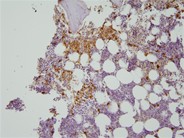

Mast cells stain positive (brown) for CD117 (c-kit). C-kit D816V mutation was detected in the bone marrow. (400×)